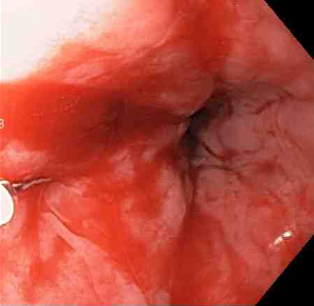

[Figure caption and citation for the preceding image starts]: Actively bleeding tear appears as a red longitudinal defect with normal surrounding mucosaFrom the collection of Juan Carlos Munoz, MD, University of Florida [Citation ends].

Actively bleeding lesions. [Figure caption and citation for the preceding image starts]: Bleeding Mallory Weiss Tear viewed on retroflexionFrom the personal collection of Douglas Adler; used with permission [Citation ends].